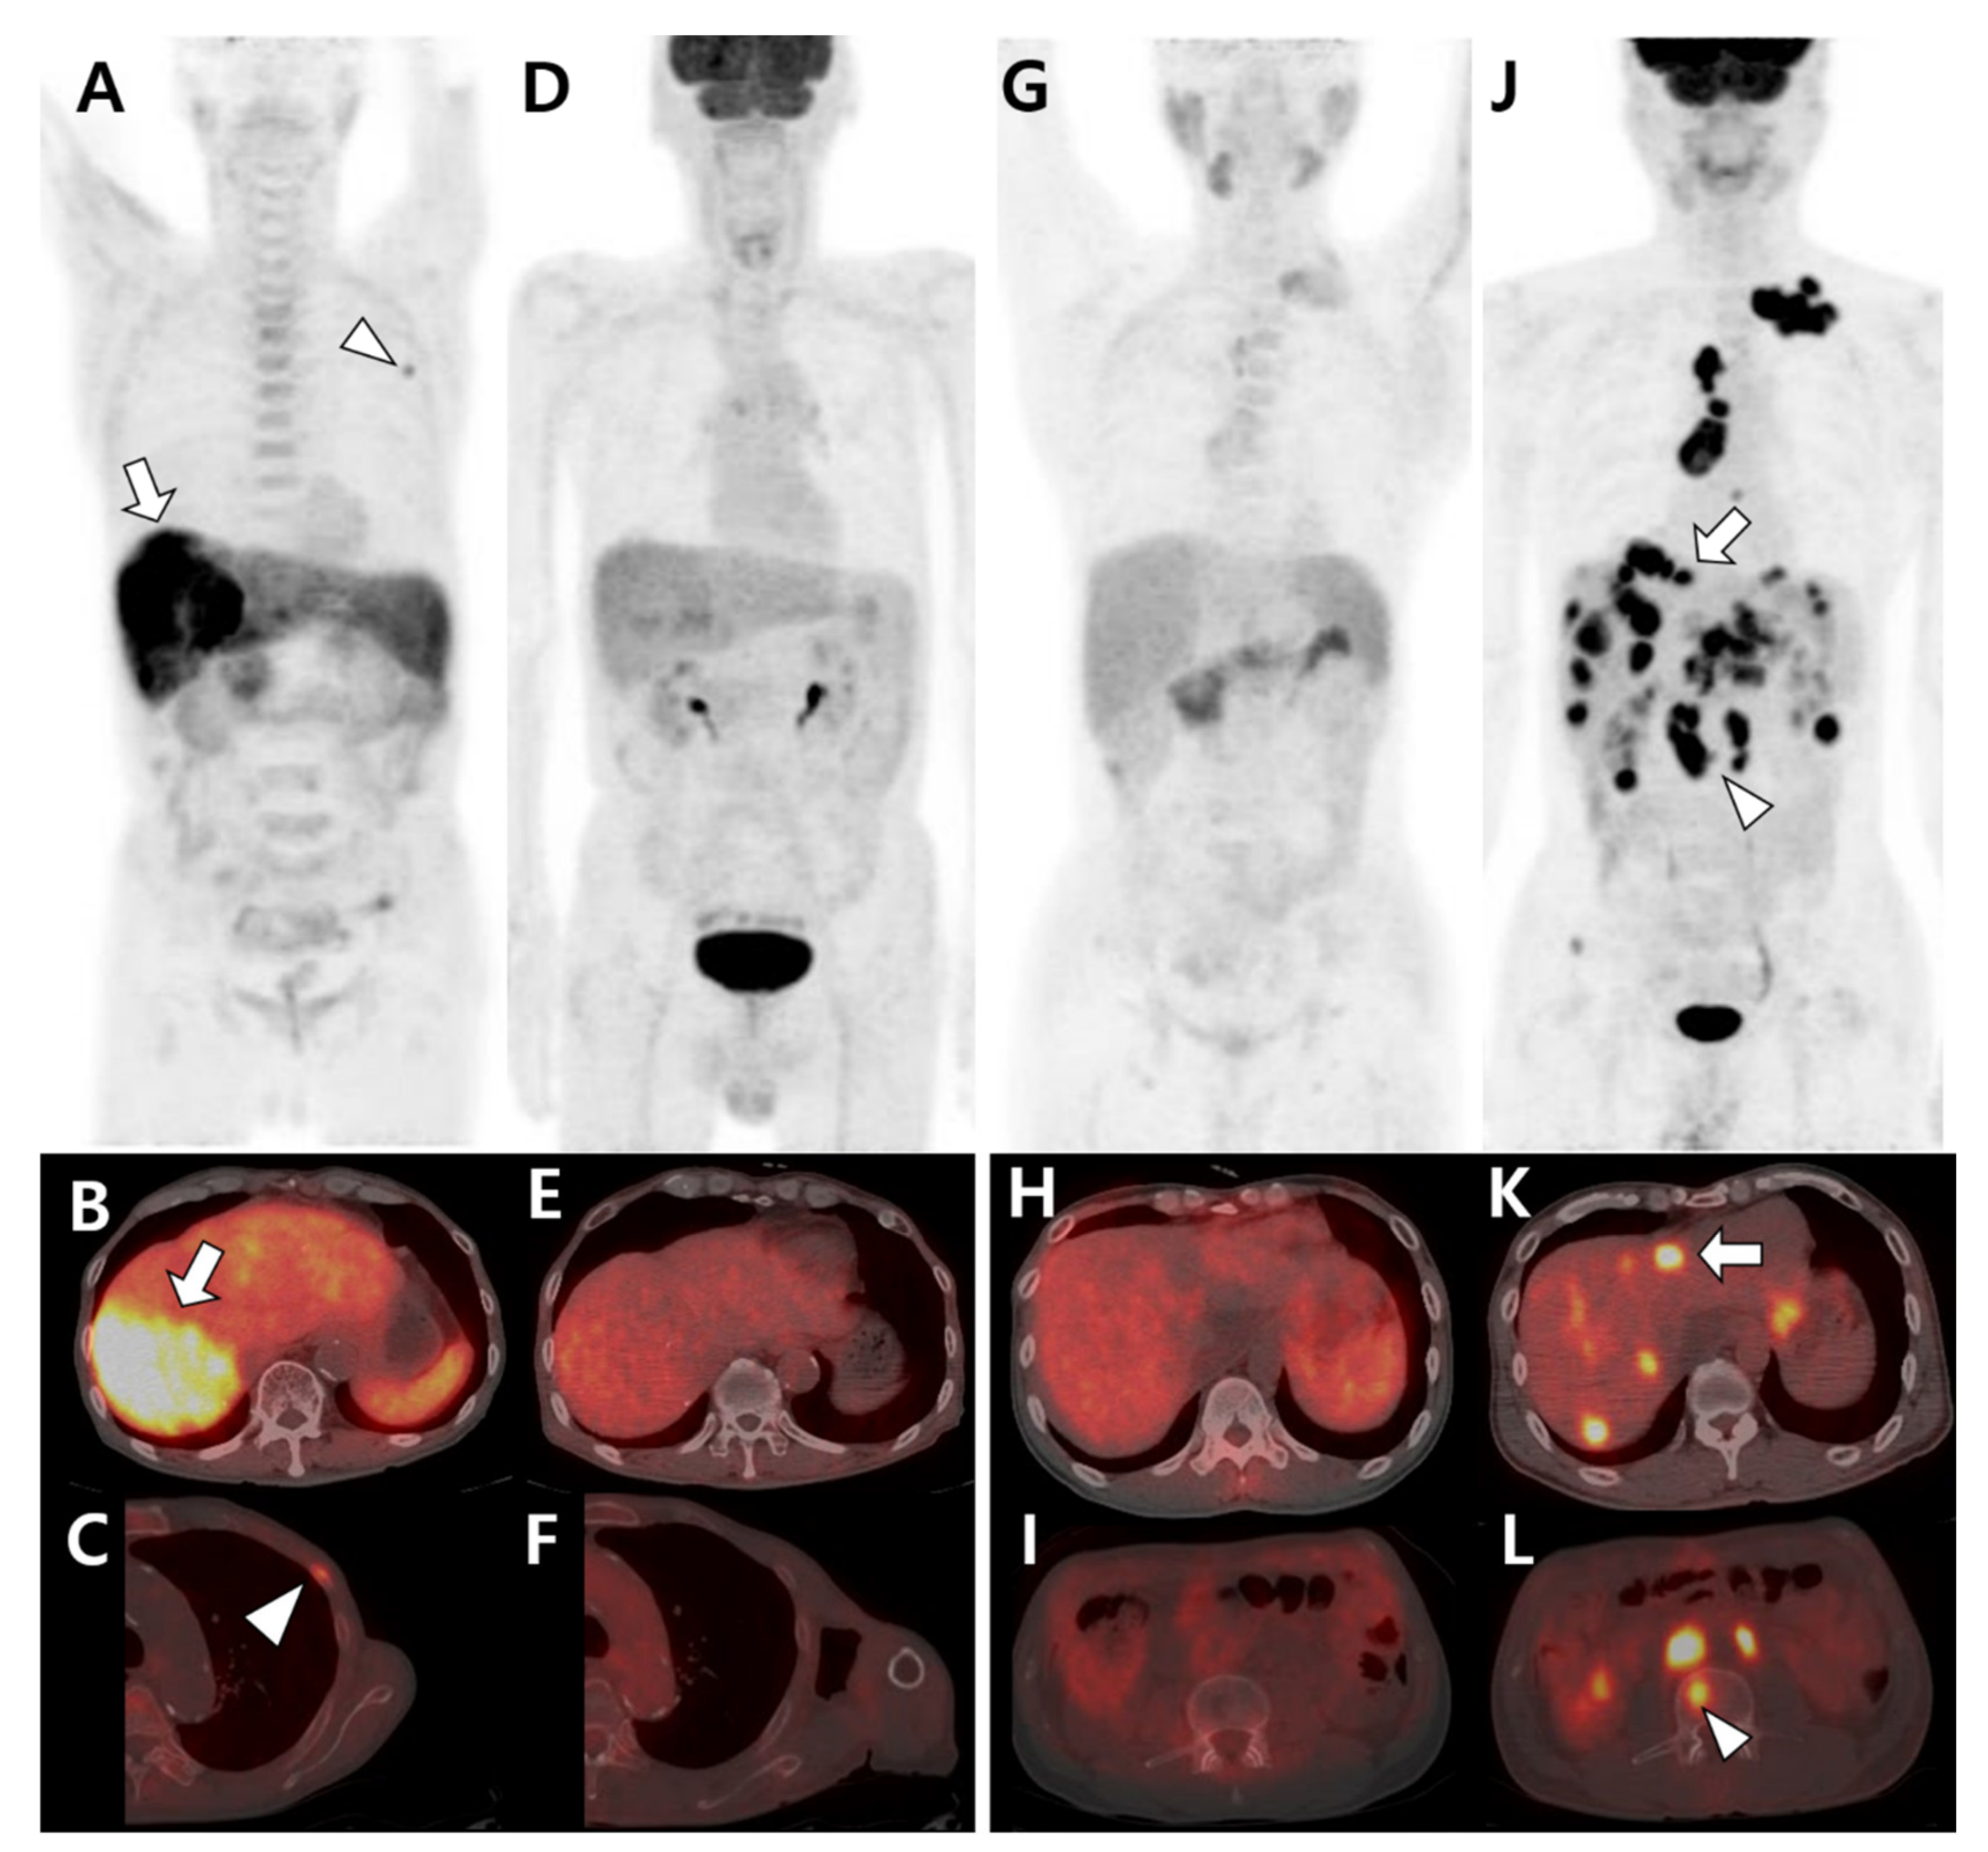

Figure 2.

Different tracer avidities of primary and metastatic sites in patients with hepatocellular carcinoma (HCC). (A–F) A 77-year-old male patient with well-differentiated HCC. 11C-acetate positron emission tomography (PET)/computed tomography (CT) (A–C) shows high acetate uptake in a primary hepatic tumor (arrow in A,B) and metastatic bone lesion in the left third rib (arrowhead in A,C). However, 18F-fluorodeoxyglucose (18F-FDG) PET/CT (D–F) shows no significant uptake in the related sites. (G–L) A 43-year-old male patient with poorly differentiated HCC. 11C-acetate PET/CT (G–I) shows mild uptake or isometabolism in the hepatic tumor (H) and metastatic bone lesion (I). In contrast, 18F-FDG PET/CT (J–L) shows intense FDG uptake in hepatic tumors (arrow in J,K) and multiple metastatic lesions in the lymph nodes and bones (arrowhead in J,L).